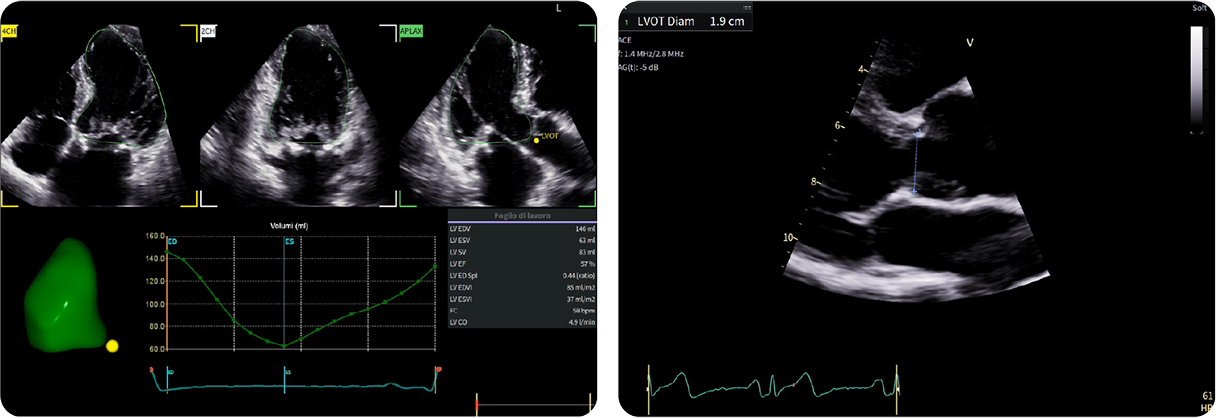

Casi clinici

Scopri come le tecnologie di imaging più innovative di GE HealthCare hanno giocato un ruolo chiave nella diagnosi di condizioni cardiache complesse.